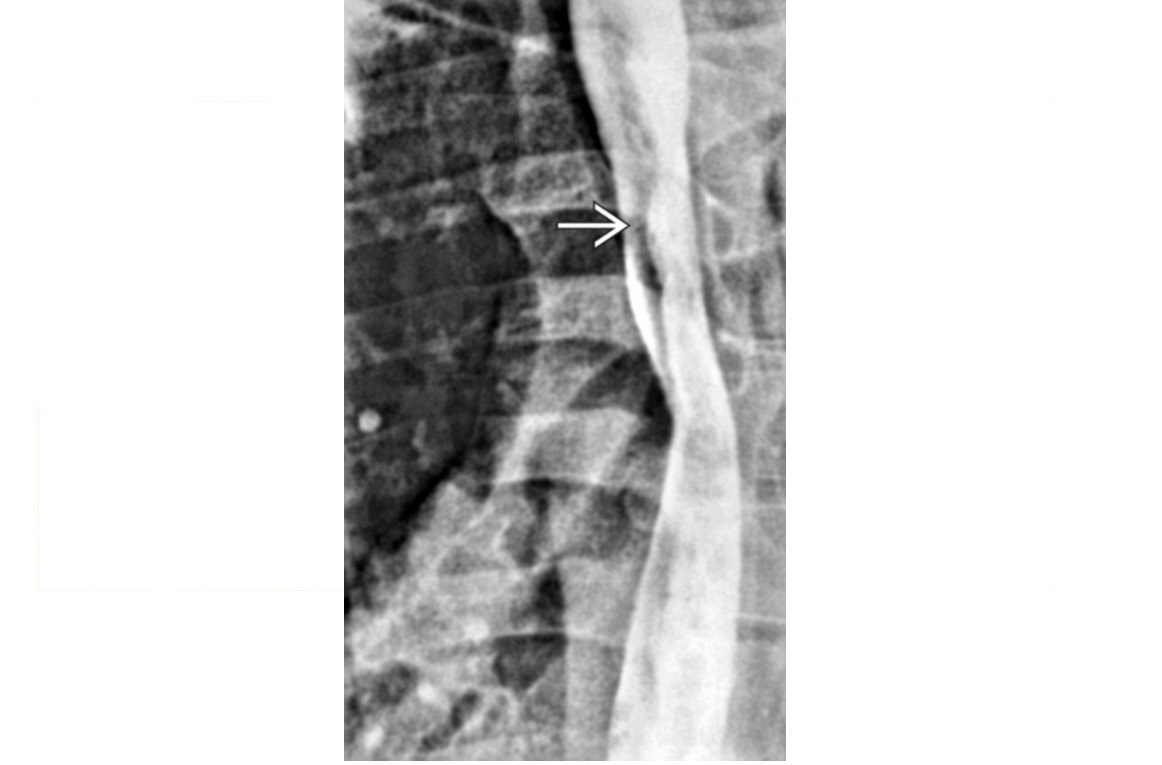

Traction diverticulum

Dysphagia in elderly person. Previous TB.

Barium-filled tented or triangular outpouching in the mid oesophagus

Acquired condition due to subcarinal or perihilar granulomatous lymph node pathology (TB, histo)

External force on oesophageal wall, such as mediastinal inflammation, that adheres and pulls on oesophageal wall